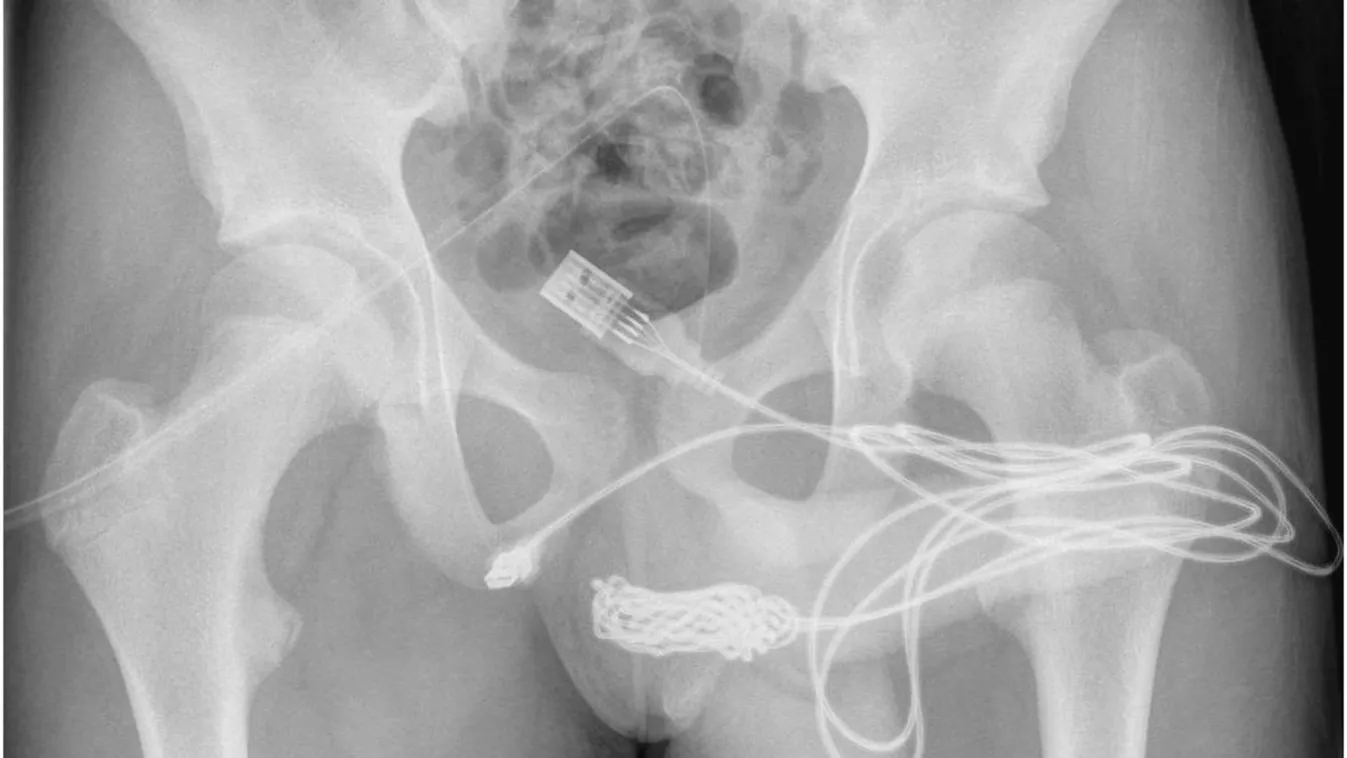

NA NE! 18+2022. 10. 03. Rémálommá vált a pénisznagyobbítás, rohantak a tűzoltók Pokoli kínokat élt át a nagyobb férfiasságra vágyó férfi.